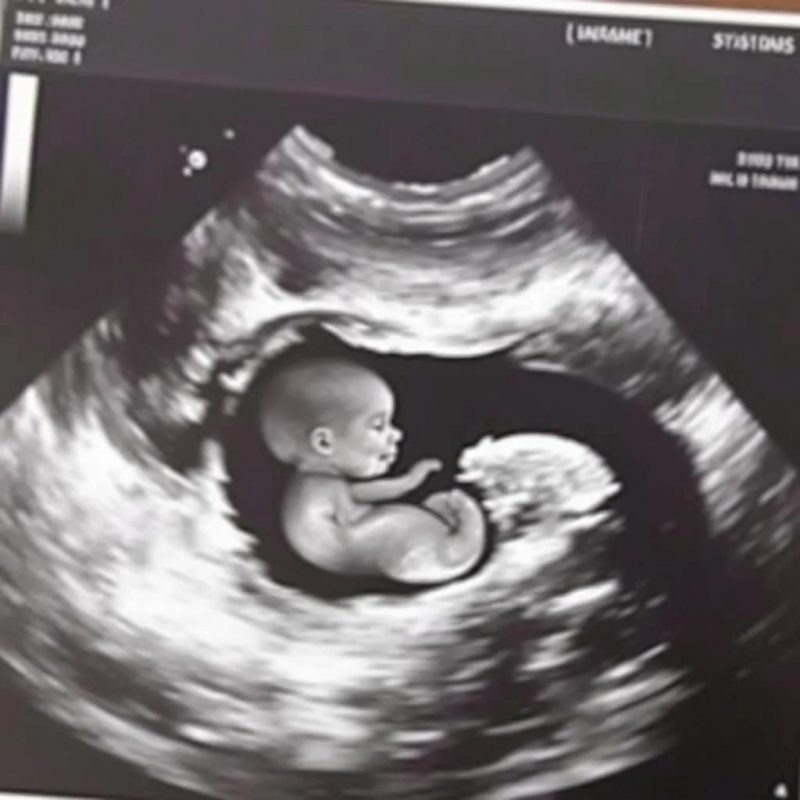

Но одно дело – это рекомендации, а другое – полный запрет или серьезное ограничение. В основе существующей на данный момент в России дискуссии о запрете абортов лежит сложный этический вопрос о признании плода в утробе беременной женщины человеком и о его праве на жизнь.

Различных точек зрения на этические вопросы, касающиеся абортов, придерживаются и ученые: что эмбрион является человеком уже с момента появления зиготы; что он не является человеком вплоть до момента рождения; что человеком плод становится не сразу после оплодотворения, а на определенной стадии беременности (чаще всего подразумеваются сроки порядка 7—8 недель, когда зародыш принимает вид «маленького человека», или в 24 недели, когда плод начинает чувствовать боль).